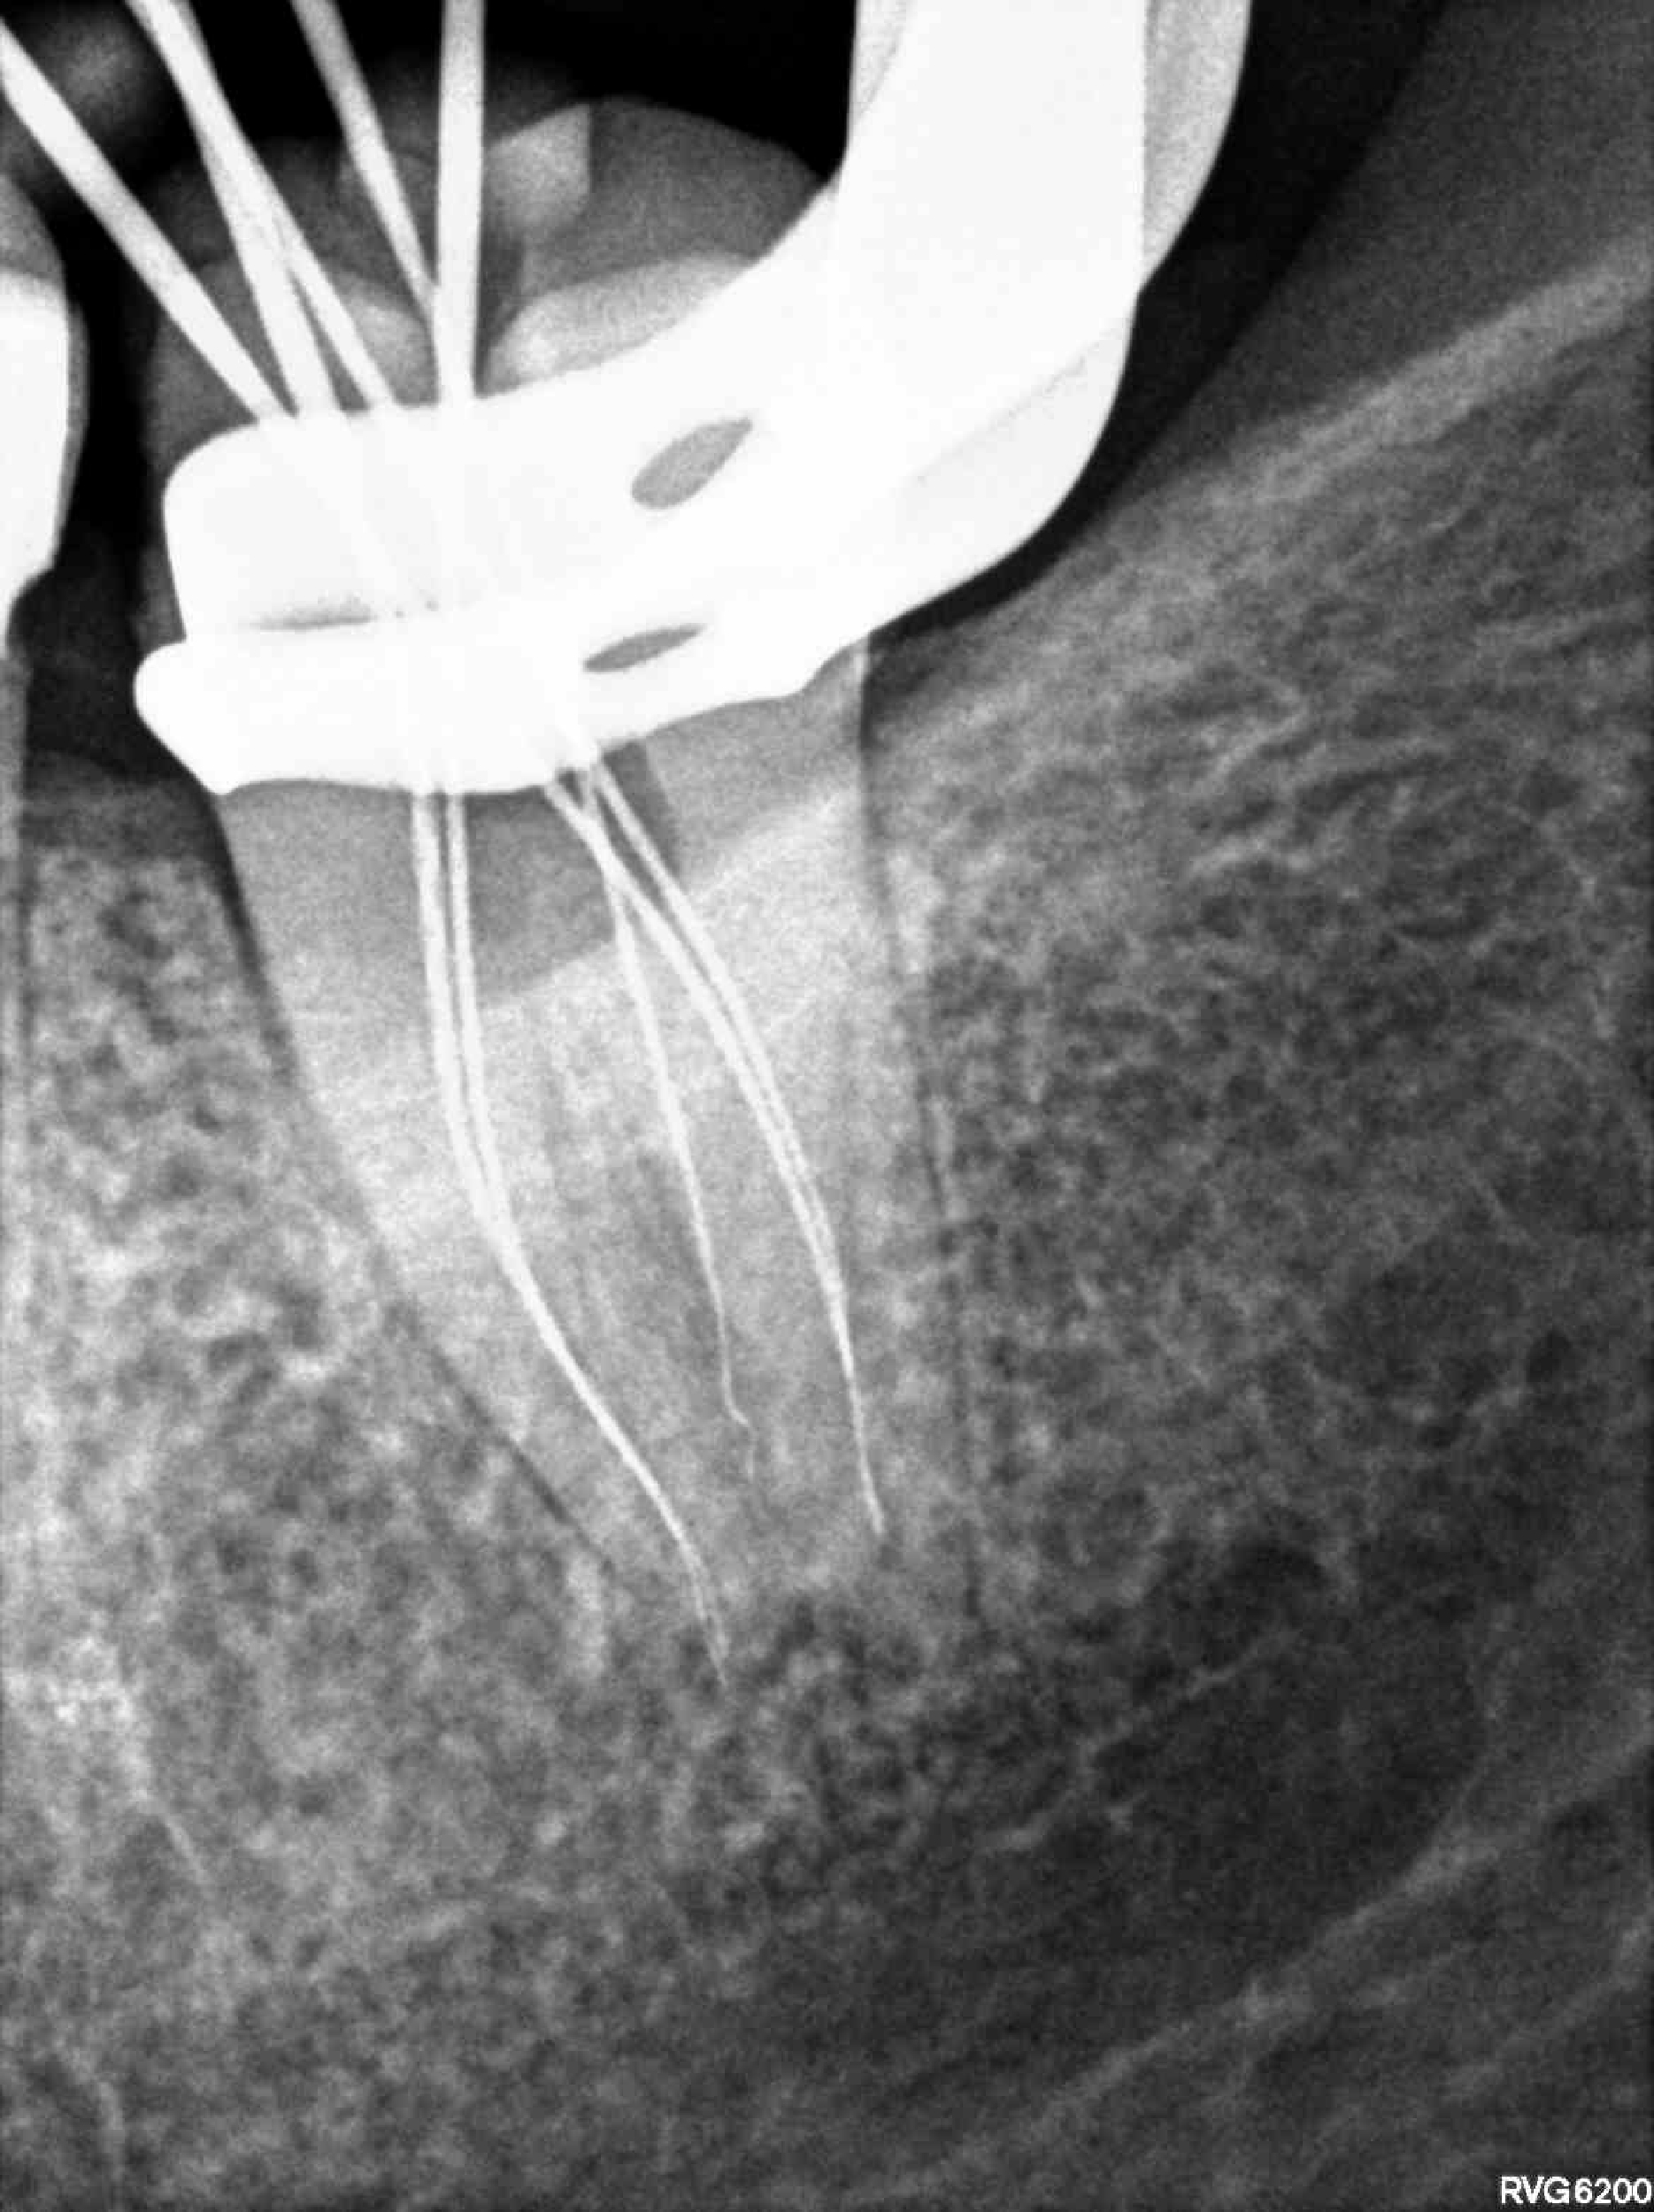

Categoría Endodoncia

Radiografías

Imágenes del tratamiento